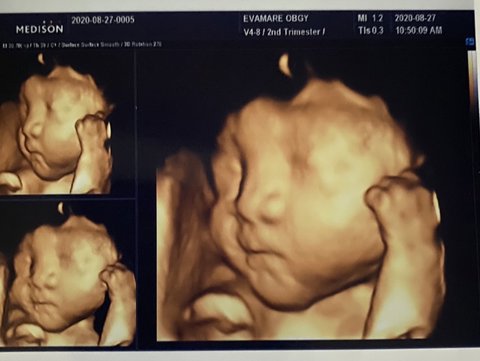

우리딸 입체초음파 사진